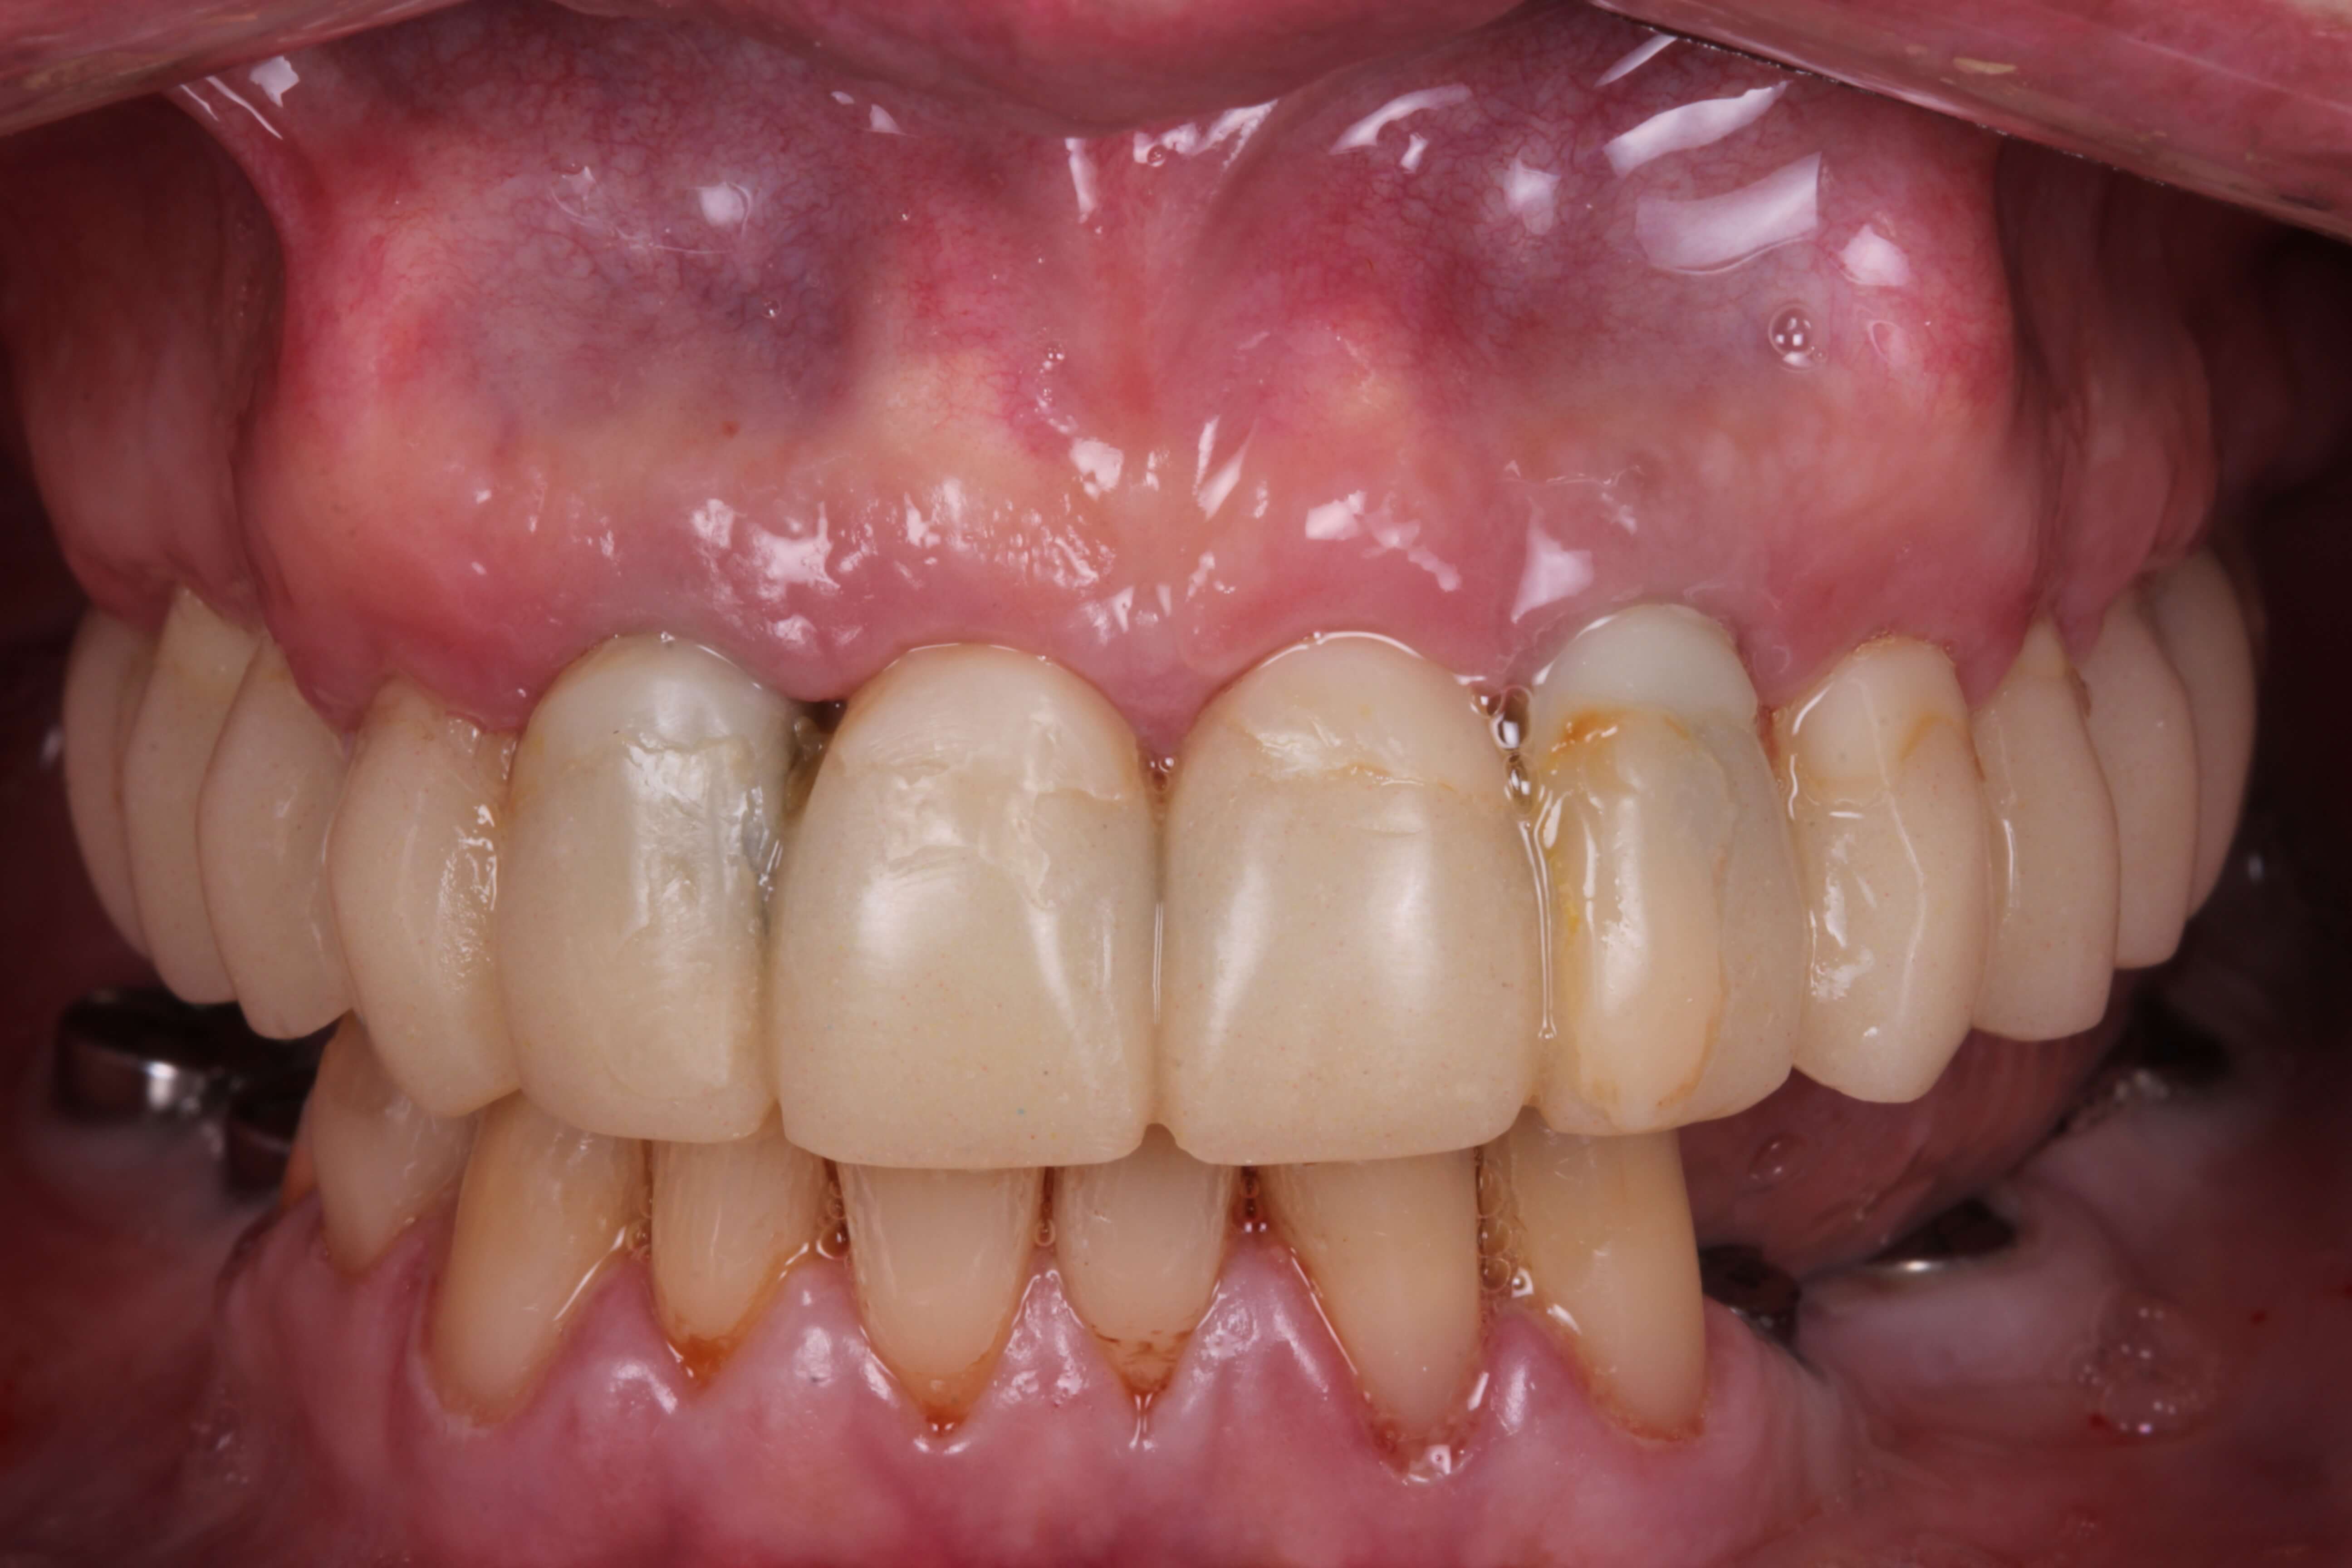

В классической методике “все на 6“ мы используем протез с искусственной десной. Но у данной пациентки ситуация осложнялась наличием так называемой “десневой улыбки”, то есть когда она улыбается у нее оголяется часть десны, поэтому традиционный протез выглядел бы неэстетично.

Через 6 месяцев пациент приехала на второй этап, во время которого мы изготовили максимальной эстетический протез на имплантатах на верхней челюсти, циркониевые протезы на имплантатах на нижней челюсти, а также скорректировали форму и цвет оставшихся зубов на нижней челюсти с помощью керамических виниров.